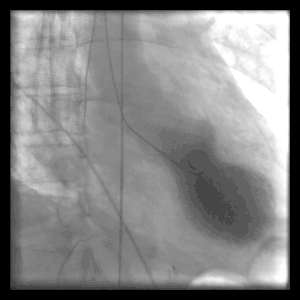

![]() Left ventriculography during systole showing apical ballooning akinesis with basal hyperkinesis in a patient with takotsubo cardiomyopathy. | |